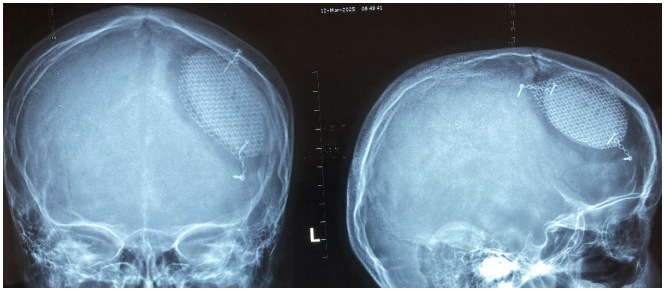

Fig 1: Sever skull bone fractures

Fig 2 &3: Post head injuries with massive brain contusion so Decompressive craniectomy done